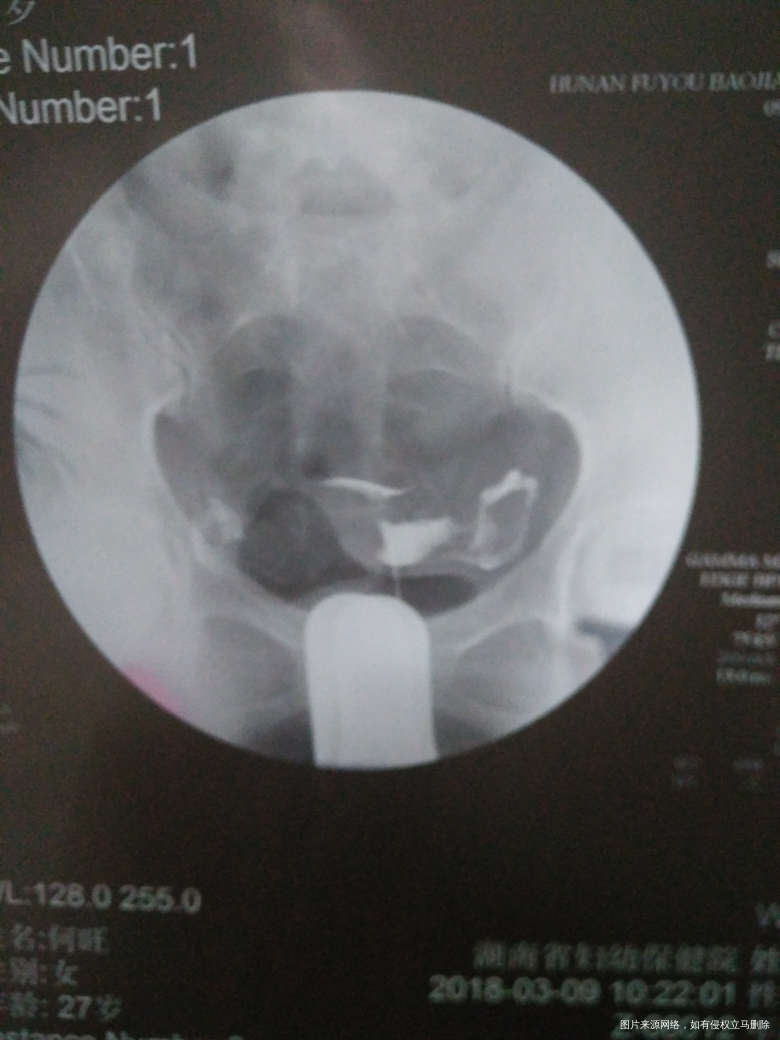

今天做了造影…结果和医生开的药物都在下面…因为拿到结果我的医生下班了…急切请各位医生帮忙看一下…给些建议…并没有流血…是不是可以不吃止血的药!

输卵管造影双侧输卵管通而不畅,有黏连,建议用中药,热敷按摩理疗等治疗后观察复查。